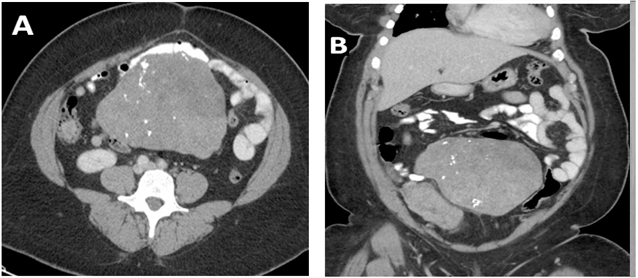

Laboratory workup showed a microcytic anemia, with hemoglobin of 9.2 gm/dL and mean corpuscular volume of 65.5 fL, which were within her normal baseline. Further, the cardiology team evaluated her, and studies from Zio Patch cardiac monitoring, stress test and echocardiogram were all unremarkable. She was started on Carvedilol 6.25mg twice a day for her uncontrolled hypertension. Pulmonary function testing demonstrated severe restrictive physiology with total lung capacity (TLC) 35% of predicted, forced expiratory volume in one second (FEV1) 34% of predicted, forced vital capacity (FVC) 31% of predicted and no response to bronchodilators. Patient was unable to perform testing for diffusion capacity of the lungs for carbon monoxide. A subsequent computed tomography (CT) scan of her chest showed multiple nodular opacities throughout both lungs, including the left lung apex and right perihilar region Figure 1.

Figure-1. CT of the chest without contrast. A) Diffuse patchy opacities in both lungs. B) Well-circumscribed masslike soft tissue nodule in the left lung apex (red arrow) and a masslike opacity in the right perihilar region (blue arrow).